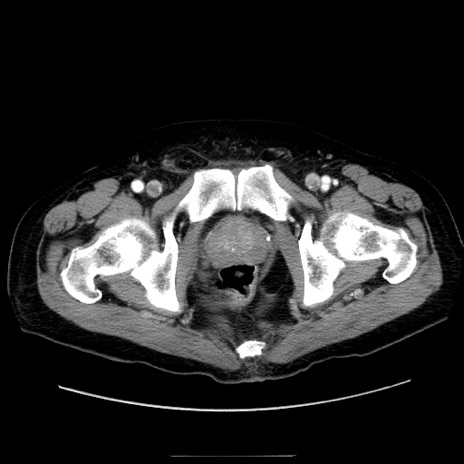

症例30(横断像)

【症例】80歳代男性

【主訴】臍周囲痛

【現病歴】約6時間前から臍下部痛が出現。次第に腹部膨隆・背部痛も生じてきたため来院。背部痛の場所は変化しない。

【身体所見】意識清明、BT 36.3℃、BP  131/87mmHg、P 87bpm、SpO2 100%(RA)、臍周囲自発痛・圧痛あり、反跳痛なし、自発痛部位に一致して板状硬あり、腹部膨隆、腸雑音減弱、CVA tenderness両側陰性。

【データ】WBC 19600、CRP 0.33